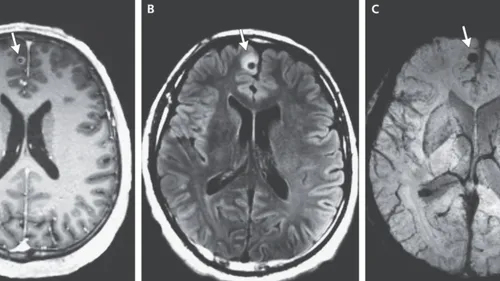

Un ver mort découvert dans le cerveau d’un homme (Photo)